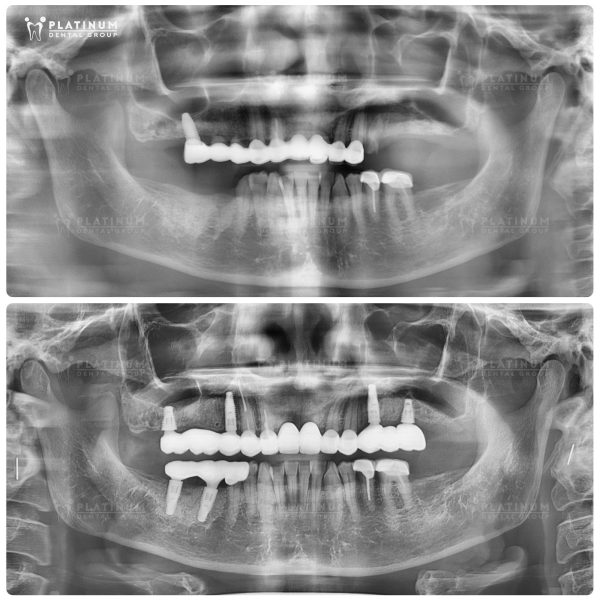

Hình ảnh trước và sau khi trồng Implant của Mr. James Harrison

Hành trình của Mr. James Harrison – đến từ Úc là minh chứng cho sức mạnh của công nghệ nha khoa hiện đại trong việc tái tạo nụ cười. Trước khi điều trị, Mr. James phải đối mặt với tình trạng răng mòn, sâu nặng và biến màu do viêm nhiễm kéo dài. Những chiếc răng cửa phía trước bị vỡ và tiêu xương nghiêm trọng, trong khi răng hàm trên và dưới gần như mất hết chức năng, khiến khả năng nhai và thẩm mỹ của anh bị ảnh hưởng lớn.

Sau khi được bác sĩ tại Platinum Dental Group thăm khám và lên kế hoạch điều trị, Mr. James đã lựa chọn phương pháp cấy ghép Implant toàn hàm với 6 trụ cho hàm trên và 6 trụ cho hàm dưới. Kết quả đạt được là một hàm răng trắng sáng, cân đối hài hòa với khuôn mặt, cùng khả năng nhai phục hồi hoàn toàn. Implant mang lại cảm giác chắc chắn, thoải mái như răng thật, giúp anh tự tin tận hưởng cuộc sống hàng ngày. Với quyết định bay từ Úc sang Việt Nam để điều trị, Mr. James đã thực sự tìm lại được nụ cười và sự thoải mái mà mình hằng mong muốn.

Kỹ thuật ALL-ON-6

Mỗi trường hợp mất răng đến với Platinum Dental Group, chúng tôi hiểu rằng khách hàng không chỉ đối mặt với khó khăn trong ăn nhai mà còn chịu ảnh hưởng sâu sắc về ngoại hình và tinh thần. Nỗi lo lắng, trăn trở về sức khỏe răng miệng luôn hiện hữu, bởi một nụ cười khỏe mạnh không chỉ là vấn đề chức năng mà còn là sự tự tin trong cuộc sống hàng ngày.

Với vị khách quốc tế này, phương án tối ưu mà Platinum lựa chọn là kỹ thuật ALL-ON-6. Chỉ sau 2 ngày cấy ghép 6 trụ Implant, một hàm răng cố định với tông màu và kiểu dáng hài hòa, phù hợp với gương mặt đã được gắn cố định lên Implant. Kết quả cuối cùng là một diện mạo trẻ trung và rạng rỡ hơn hẳn, giúp anh lấy lại sự tự tin và niềm vui trong cuộc sống.